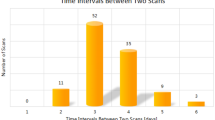

This is a secondary analysis of prospectively acquired data approved by the hospital institutional board committee. We performed a retrospective chart review of 463 patients who underwent a CT Chest for suspected COVID-19 infection between April 1st, 2020, and March 31st, 2021. Patients were grouped based on the CT chest obtained protocol: ultra-low dose or full dose. The likelihood of suspicion of COVID-19 infection was classified on a Likert scale based on the probability of pulmonary involvement. For each group, the sensitivity and specificity of CT were compared to nasopharyngeal swab as standard of reference. The median dose length product and duration of apnea were compared between both groups using two-tailed Mann–Whitney U test. The aim of this study is to share our experience of reducing radiation dose in COVID-19 patients by using an ultra-low dose CT chest protocol on a 16 row multidetector CT scan in a hospital with limited resources.

A threshold of 1 millisievert was used to divide our population in two groups. There were 269 regular CT exams with a full dose (FDCT; estimated dose ≥ 1 millisievert) and 194 exams with an ultra-low dose CT (LDCT; estimated dose < 1 millisievert). The biological test (RT-PCR or Rapid Antigen test) was considered our reference standard for the diagnosis of COVID-19 infection.

DLP and duration of apnea

The median DLP was higher 341.1 mGy*cm [IQR, 239.1–443.2] in the FDCT group compared to the LDCT group 30.8 mGy*cm [IQR, 28.9–32.7]. The difference was statistically significant (P < 0.0001).

The median duration of apnea was 13.29 s [IQR, 10.85–15.73] for the FDCT group and 8.27 s [IQR, 7.69–8.85] for the LDCT group. The difference was statistically significant (P < 0.0001).